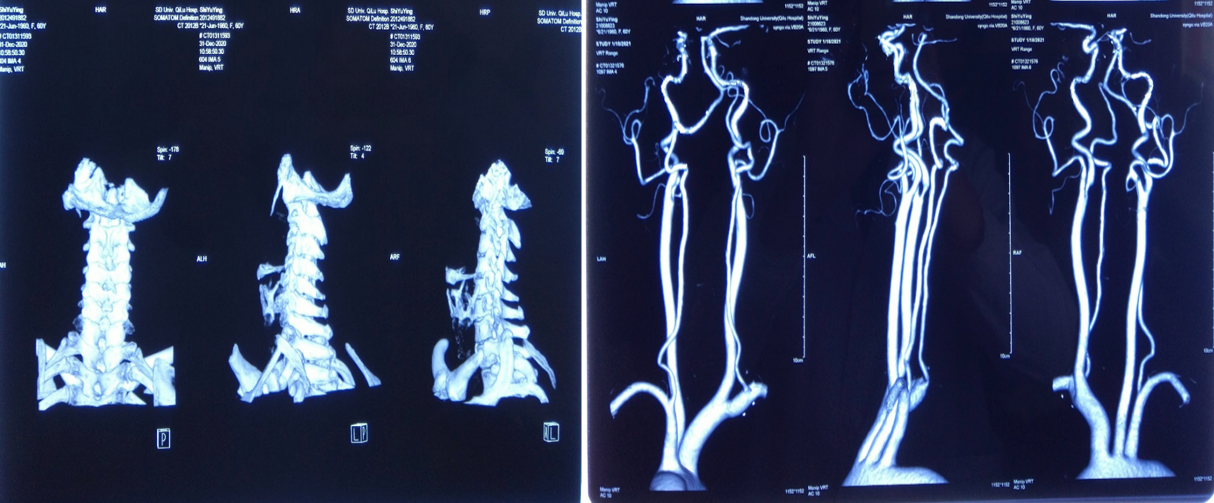

颈椎CT:

颈椎退行性变,C2/3、C3/4、C4/5、C5/6、C6/7椎间盘突出并C4/5水平椎管狭窄;符合颅底凹陷症合并寰枕融合,寰枢关节脱位CT表现。

颈部血管CTA:

颈动脉硬化并多动脉狭窄,以右侧颈内动脉起始处为著,呈中度狭窄。

患者术前部分影像学资料

影像学资料显示寰枢椎脱位,脊髓受压明显